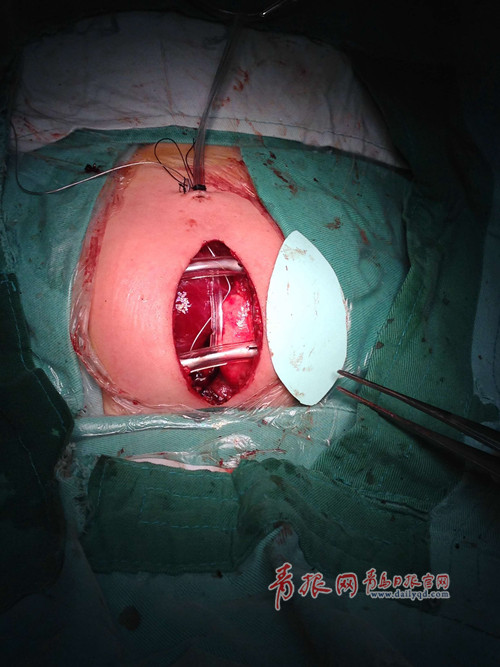

????值得一提的是,由于手術(shù)難度高,時(shí)間較長,患兒心臟在術(shù)后不可避免地出現(xiàn)水腫,無法放回胸腔立即縫合,傳統(tǒng)情況下會(huì)讓患兒保持胸腔開放一段時(shí)間,心臟裸露在外。而邢泉生教授自2009年就從美國引進(jìn)了一種人工皮膚,可以在術(shù)后暫時(shí)縫合在患兒胸腔保護(hù)水腫的心臟,從而減少了患兒感染的幾率,待心臟水腫消除后再取下人工皮,縫合胸腔。這在國內(nèi)也是唯一使用這項(xiàng)技術(shù)手段的醫(yī)院。

手術(shù)照片